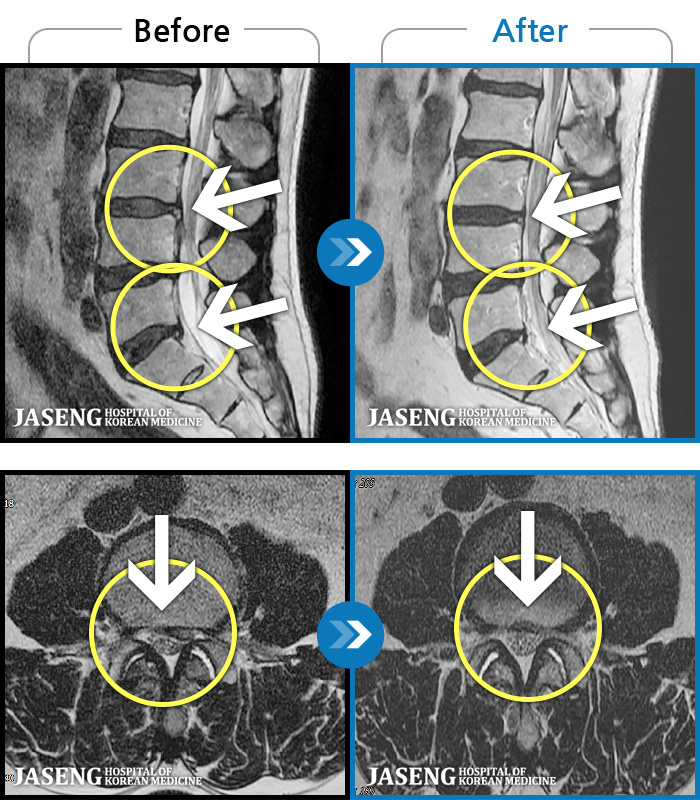

허리디스크

인천 · 강아현 원장

좌측 허리 통증 및 골반 통증이 심하여 걷는 것도 힘든 상태로 내원하셨습니다.

촬영시기

2024.05.08 ~ 2025.11.12

2025.11.14

조회수 128